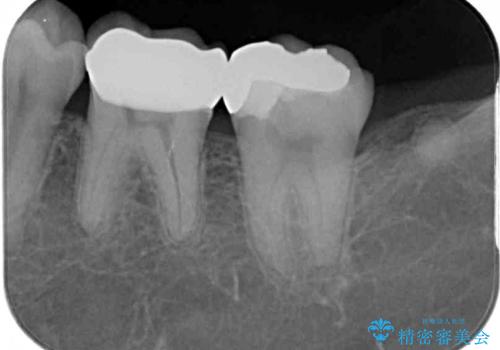

手前の歯はむし歯の範囲が広いためオールセラミッククラウンにて、最後方歯は部分的なむし歯であったのでPGAインレー(プラチナゴールドインレー)にて治療を進めることとしました。

仮詰めの状態が良くなかっただけで、むし歯が神経組織にまで及んでいることはなく、無事に治療を終えることができました。